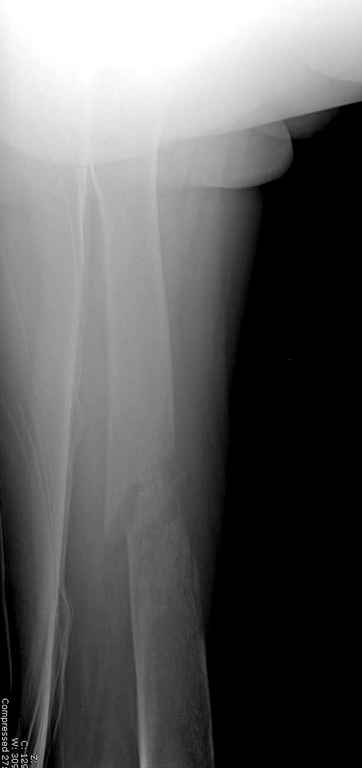

Здесь случай 66 летней пациентки со спонтанными болями в левой нижней конечности, обратилась в приемное, сделаны снимки бедра и КТ.

Патологический перелом бедра, конечность на вытяжении.

Известно, что многие из нас независимо от метода лечения и стадии первичной опухоли проводят интрамедуллярное штифтование при различных патологических состояниях бедра, включая патологические переломы.

В зависимости от характера опухоли некоторые патологические переломы имеют риск кровотечения во время операции. Множественные литературные данные подтверждают, что надо проявить осторожность при интрамедуллярном остеосинтезе при неизвестных опухолях, особенно где имеется подозрение на Renal Cell Carcinoma. (RCC- hypernephroma) http://www.bonetumor.org/tumors/pages/page64.html

Со слов, больная ничем не болела, только последние 3 месяцев чувствовала боли в бедренной области. КТ брюшной полости подтвердил увеличенную правую почку. (5-6)